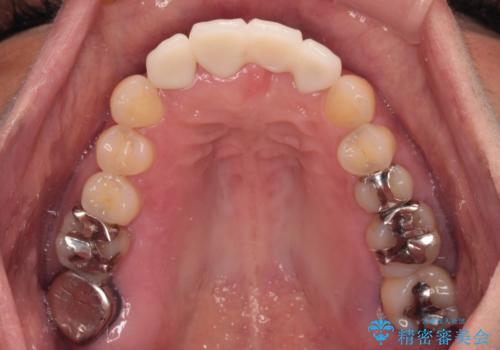

中途半端な矯正治療と前歯の欠損 再矯正とオールセラミッククラウンによる補綴治療

- 矯正治療を行ったものの、隙間やデコボコが多く、欠損している前歯も気になるとのことで来院された患者様です。

当初はセラミック治療だけを希望されていましたが、上下前歯のデコボコが顕著であったため、セラミッククラウンにて治療する前に再度矯正治療を行った方が仕上がりがきれいになると説明し、再矯正を行うこととしました。

矯正治療により前歯横幅のバランスを整えた後に、上顎前歯をオールセラミックブリッジにて補綴治療を行うこととしました。